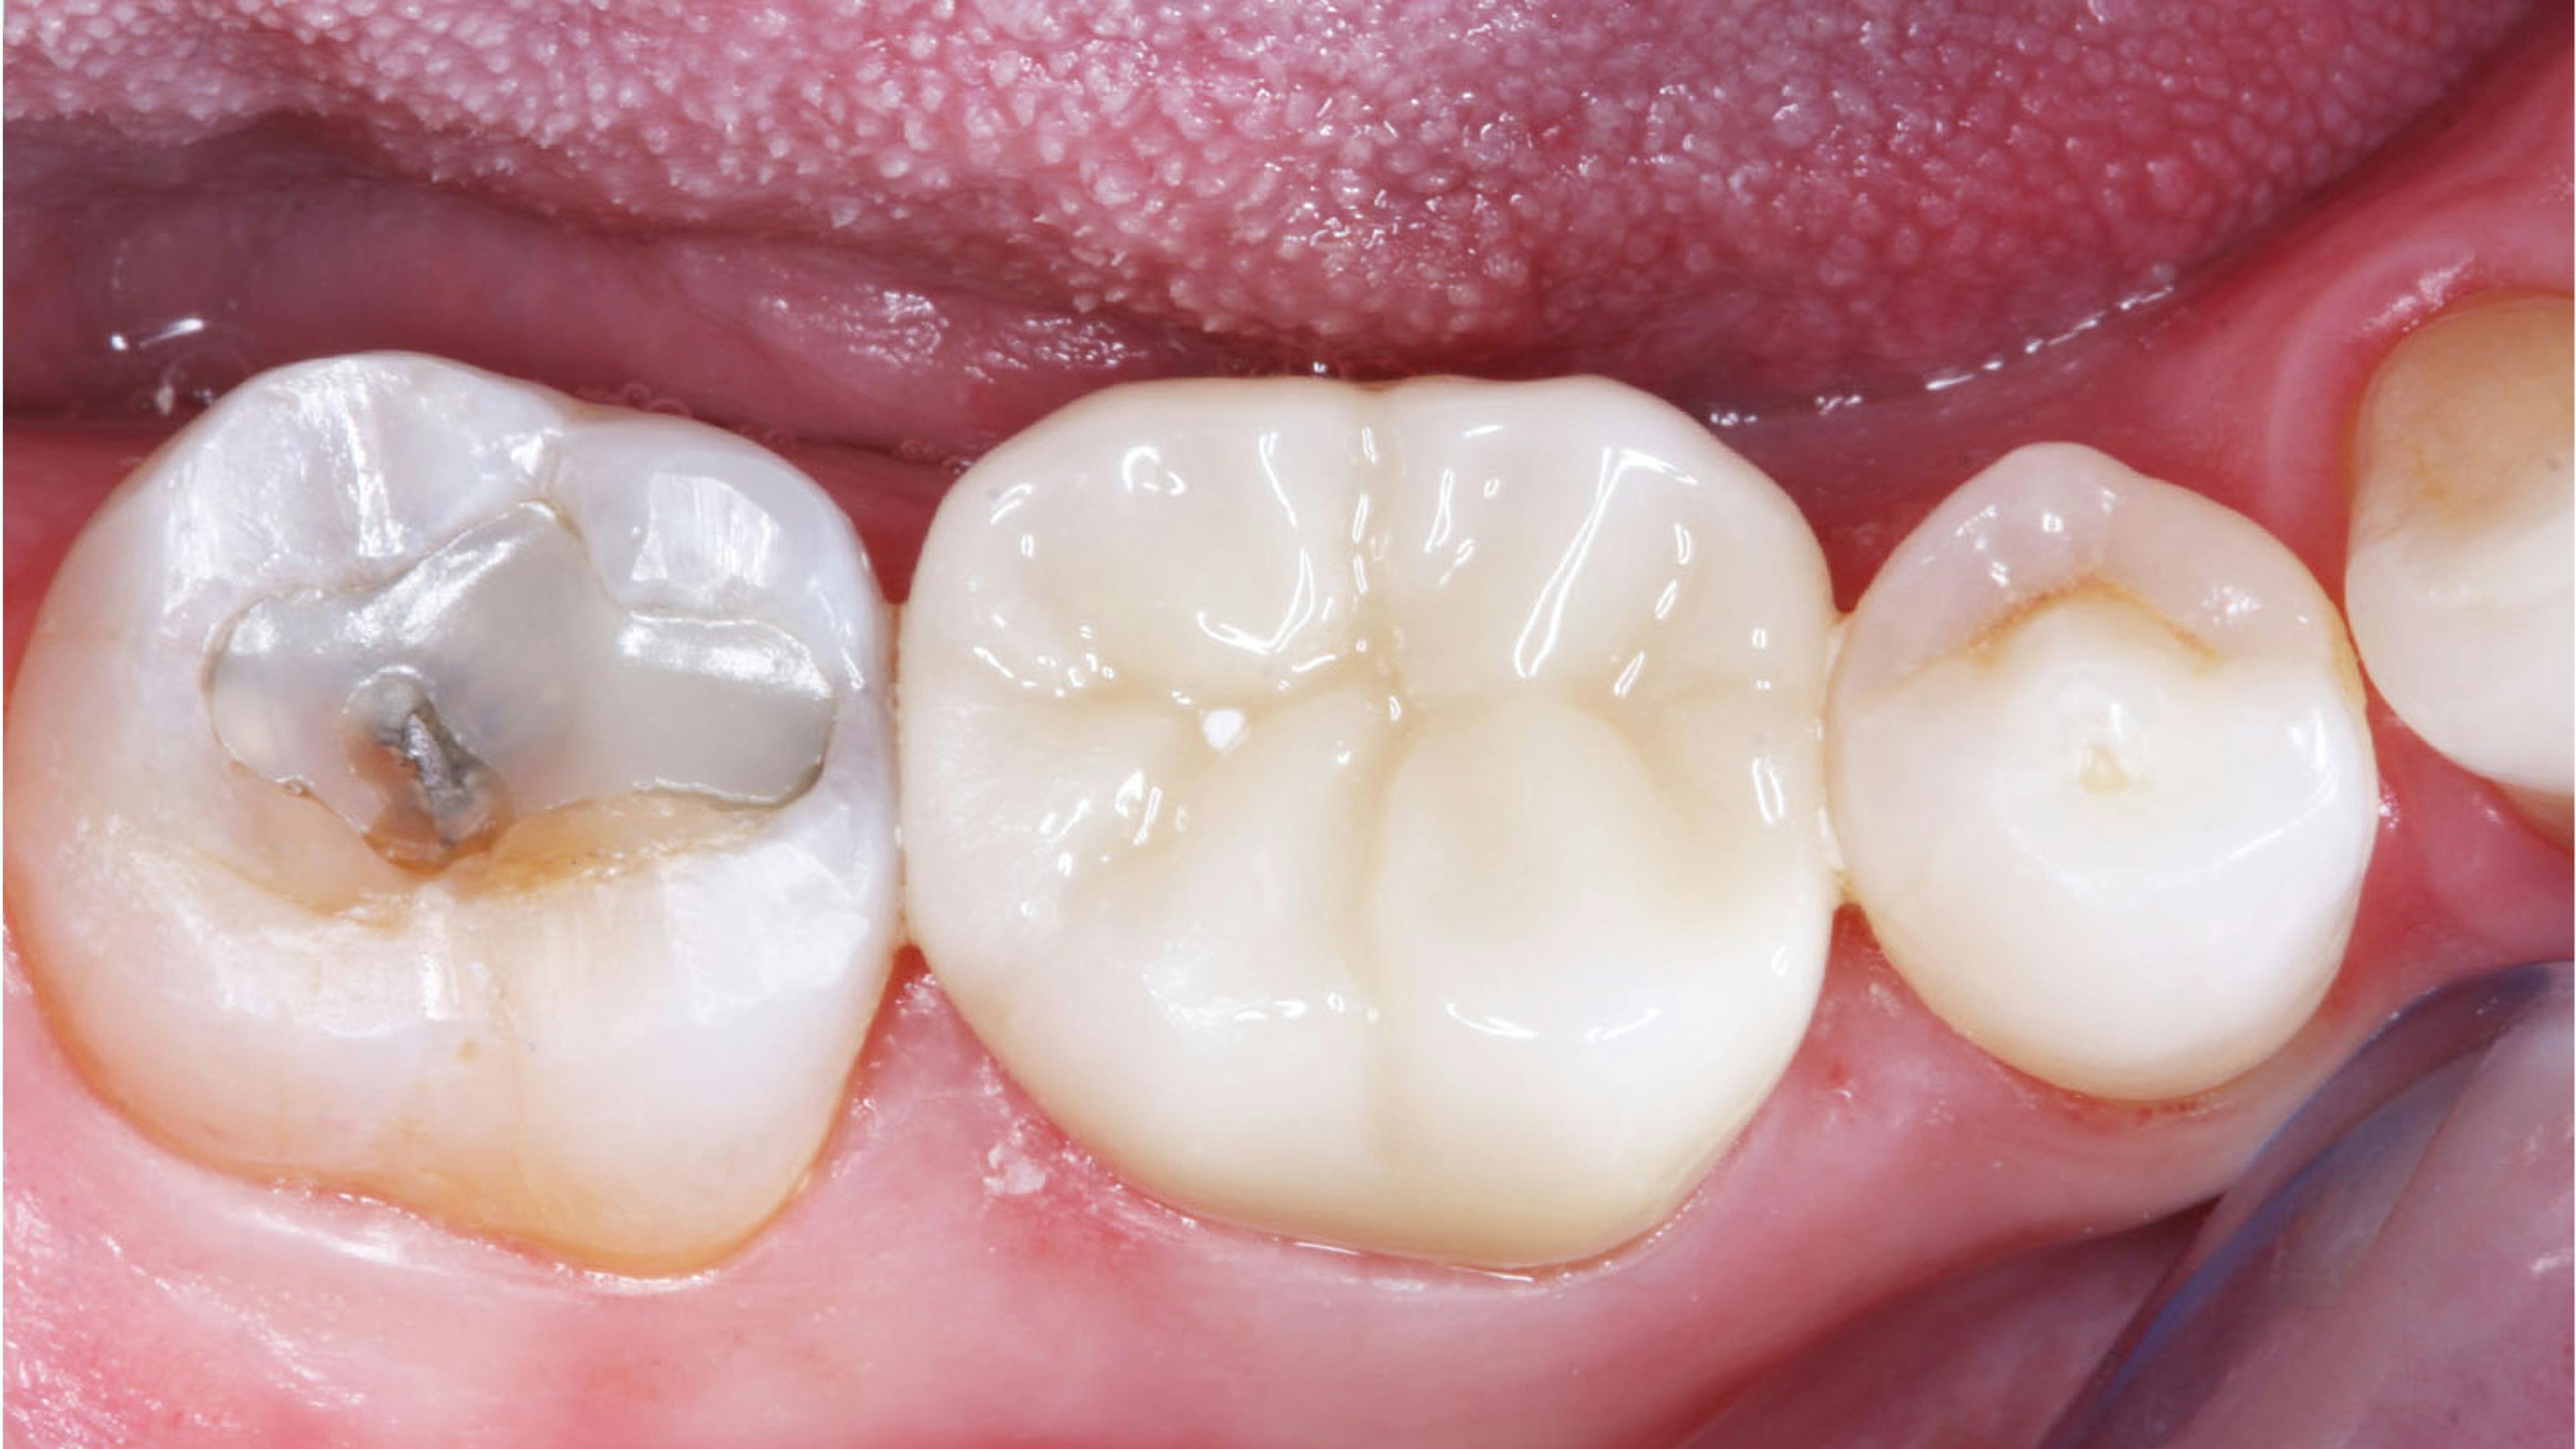

🦷 New restoration types make occlusion knowledge mandatory